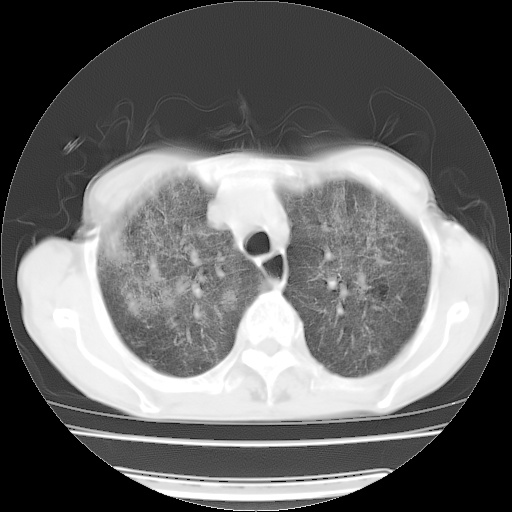

病人发热、气促就诊。原二周前已行ct扫描,当时诊断为双肺下叶、右肺中叶支气管扩张并感染,双肺上叶片状渗出性病变。今天复查胸部ct,双肺下叶支气管扩张并感染病灶较前明显吸收,但双肺上叶渗出性病变较范围较前明显增大。

现传今天ct图像给大家讨论。

双肺多发大片状、斑片状高密度渗出影,部分实变,考虑病毒性肺炎。